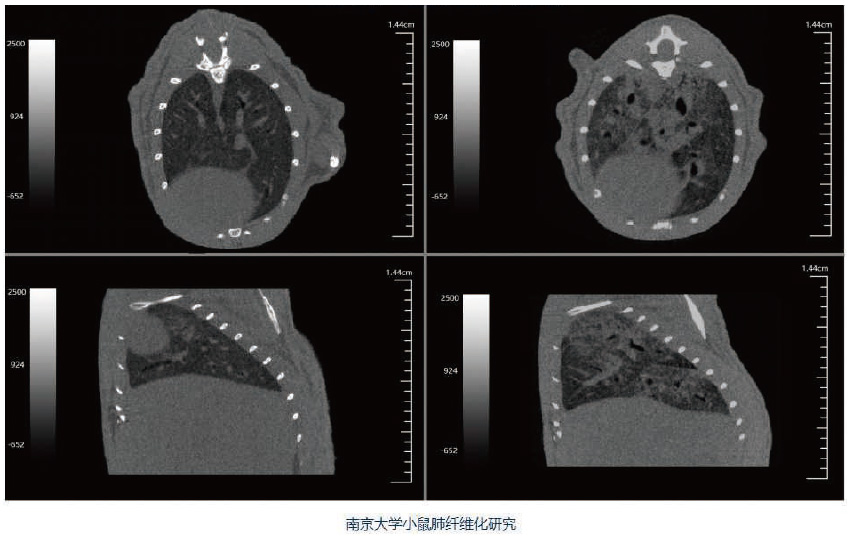

Hiscan VM Pro是一款快速灵活的活体显微CT,主要用于动物实验。其所用的锥束X射线可以看到样本的内部结构,最高分辨率可达18μm。可做小动物全身扫描,如小鼠、大鼠等。同时,可以扫描所选择的感兴趣区域,例如小鼠和大鼠的头部、脊椎、前肢 、后肢等。根据样本尺寸不同配以不同尺寸的扫描床,独特设计的扫描床可以防止小动物逃逸落进机器内。

Hiscan VM Pro配有高精度自适应呼吸门控,可根据呼吸周期的变化动态调整图像采集速度,有效减少呼吸带来的胸廓运动伪影。防护机壳配有麻醉气体传输接口以及多种生理监控设备接口。X射线机壳防护安全可靠,操作人员无需额外防护。同时配有安全连锁装置,仓门打开时自动关闭X射线,避免误操作,保证操作人员安全。

广泛应用于骨骼疾病、肿瘤疾病、心血管疾病、炎症疾病、代谢疾病、免疫学、药效评价、生物材料等学科的临床前研究。